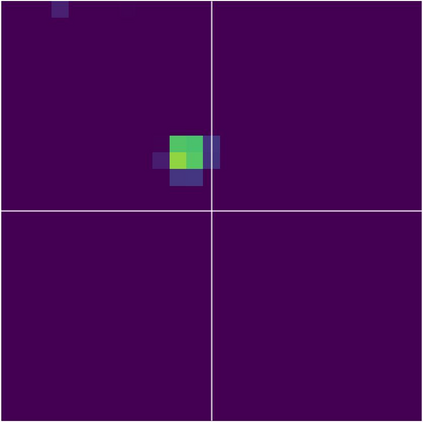

Various imaging modalities allow for time-dependent image reconstructions from measurements where its acquisition also has a time-dependent nature. Magnetic particle imaging (MPI) falls into this class of imaging modalities and it thus also provides a dynamic inverse problem. Without proper consideration of the dynamic behavior, motion artifacts in the reconstruction become an issue. More sophisticated methods need to be developed and applied to the reconstruction of the time-dependent sequences of images. In this context, we investigate the incorporation of motion priors in terms of certain flow-parameter-dependent PDEs in the reconstruction process of time-dependent 3D images in magnetic particle imaging. The present work comprises the method development for a general 3D+time setting for time-dependent linear forward operators, analytical investigation of necessary properties in the MPI forward operator, modeling aspects in dynamic MPI, and extensive numerical experiments on 3D+time imaging including simulated data as well as measurements from a rotation phantom and in-vivo data from a mouse.